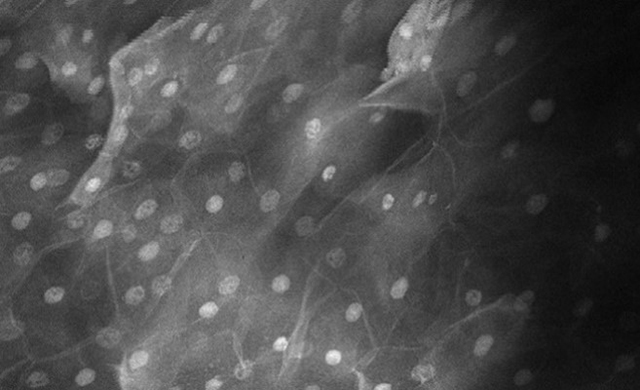

InVivage® is an intra-oral digital endomicroscope that offers the power of single-cell oral imaging at your fingertips. InVivage® by Optiscan is built with our unique patented 3D imaging technology, providing live microscopic oral imaging solutions in optimal resolution, and unlimited image capture to assist in immediate informed decision making.

- Optimized for imaging cellular architecture, in clinical and research settings, at single cell level

- Produces real-time, high-resolution images at 1000x real magnification

- Images easily interpreted using recognized WHO diagnostic criteria for oral epithelial dysplasia

InVivage® can help clinicians distinguish normal, precancerous and cancerous oral tissue.